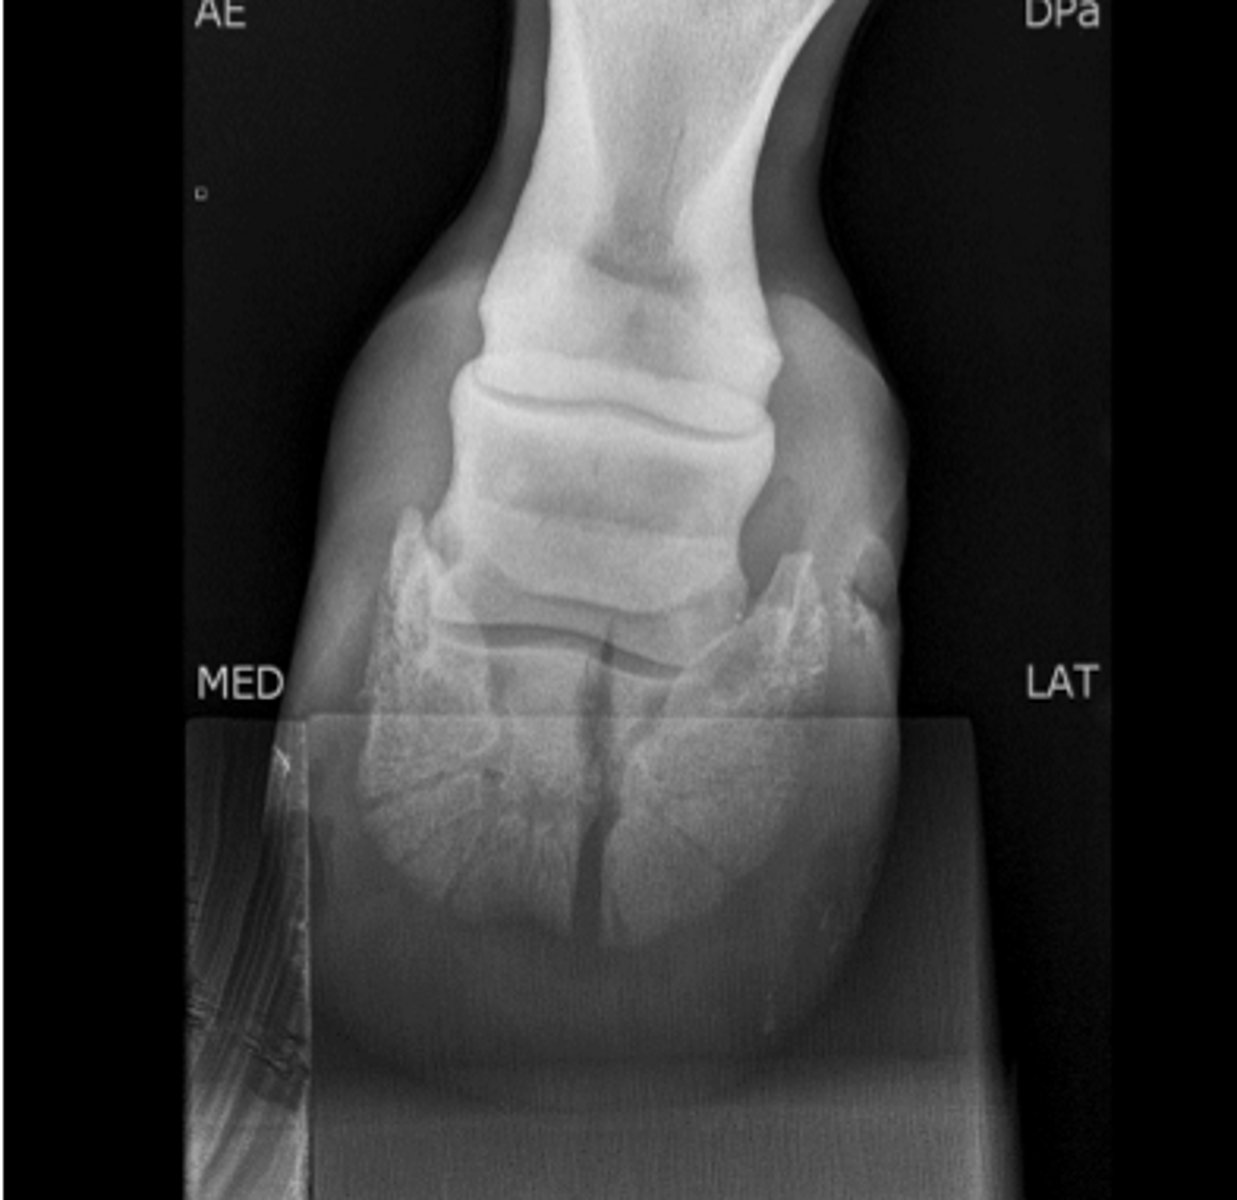

What joint need to be stabilized?

Lag screw fixation

How should this fracture be treated?